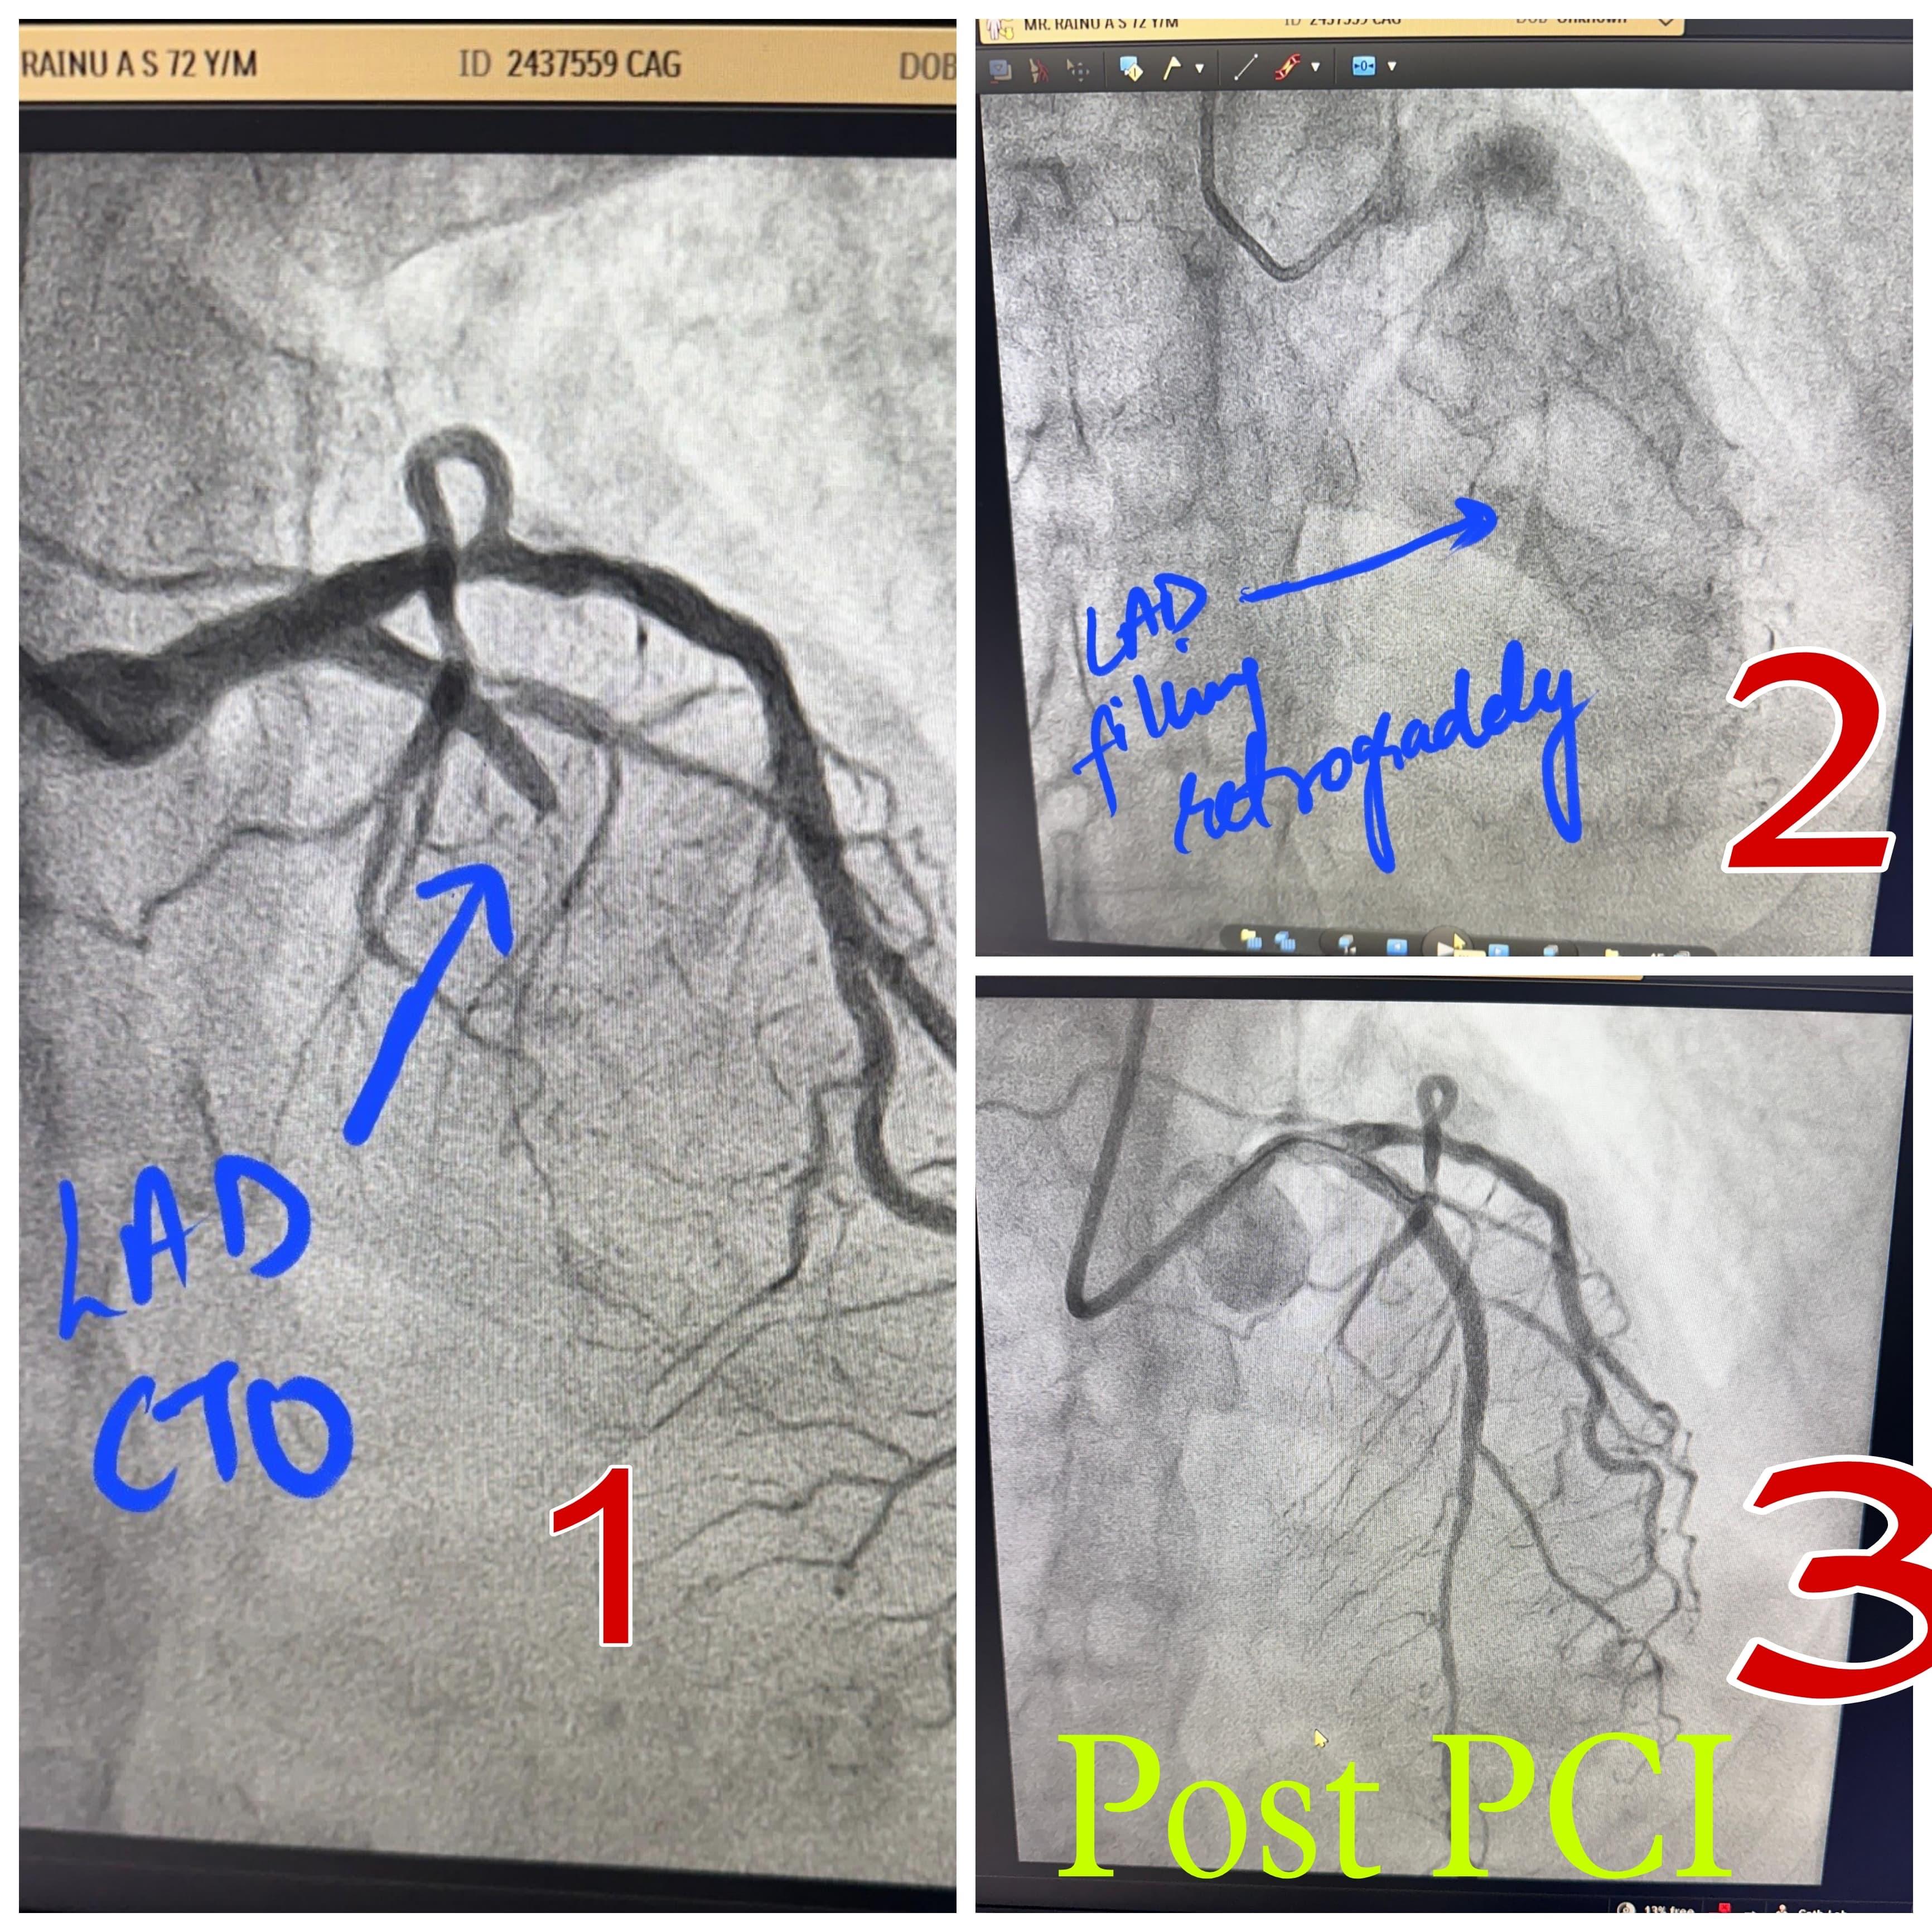

Angioplasty/Stenting

Angioplasty, also called Percutaneous Coronary Intervention (PCI), is a medical procedure used to open narrowed or blocked arteries in the heart. It restores blood flow and helps prevent heart attacks or other cardiac emergencies.

A thin tube called a catheter is inserted through an artery—usually in the groin, wrist, or arm. At the tip of the catheter, there's a small balloon. Once it reaches the blocked artery, the balloon inflates. This pushes plaque against the artery walls, widening the passage.

What Is a Stent?

A stent is a tiny mesh tube placed in the artery during angioplasty. It keeps the artery open long-term. Most modern stents are drug-eluting, meaning they slowly release medication to prevent re-narrowing.